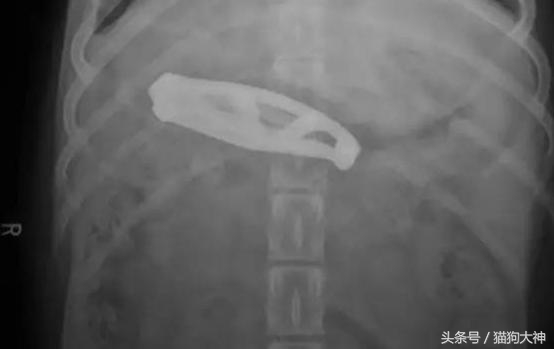

这只狗狗趁主人不注意,吞下了一把折叠刀,发现不对的主人赶紧送它去了医院。

所幸主人把不用的小刀折叠好了,狗狗并没有什么大碍。